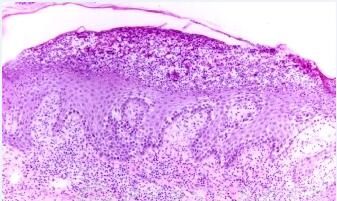

艾滋病感染性皮肤损害-真菌感染:发生于口咽部的鹅口疮是*缺陷较早出现的症状。此外,HIV感染者常出现浅表真菌感染,如体股癣、手足癣、花斑癣、甲真菌病,皮损较非HIV感染者广泛,且不典型,需做刮屑镜检和培养。l0 一13 艾滋病患者可发生隐球菌感染,皮损常表现为传染性软疣样损害,中枢神经系统易受累。还可出现马尔尼菲青霉菌感染,以网状内皮系统受累为特征,70 病人可有皮肤损害。